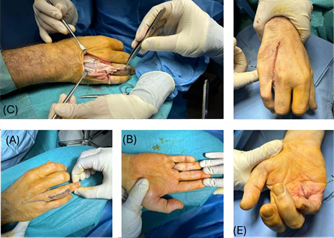

An orthopedic re-examination took place after 6 months. During the examination the patient was diagnosed with pseudoarthrosis (Figure 2) and was advised to undergo arthrodesis of the proximal phalanx which he declined due to the loss in mobility inherent to the procedure. On the other hand, the patient proposed a Ray amputation which after clinical discussion and psychological approval of the patient took place successfully (Figure 3).

Figure 2: (A) X-Ray of the finger prior to the amputation (B,C) Preoperative photograph of the hand.

Figure 3: Photographs of the dorsal (a) and volar (b) aspects of the hand demonstrating the markings for a v-shaped incision for resection of the index finger and intraoperative (c, d, e) photographs.